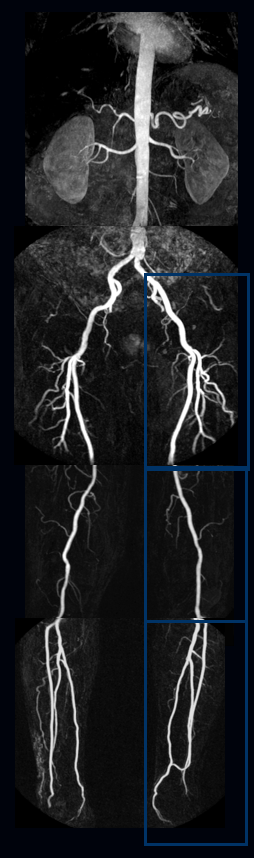

常用血管成像模式的原理和特点(超声多普勒、CTA、MRA、DSA等);